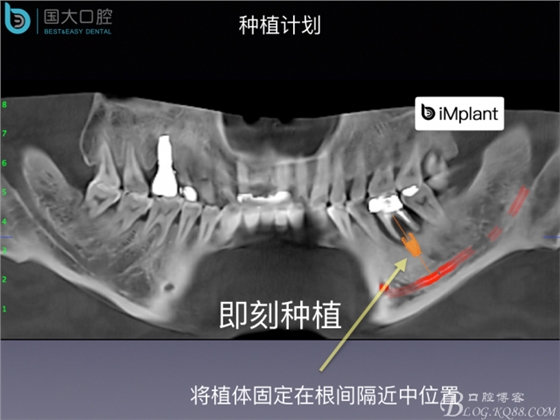

20160715154343_73038.jpeg